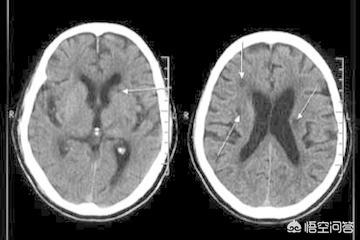

Différence entre infarctus cérébral et infarctus cérébral lacunaire

1. infarctus cérébral :Le terme "infarctus cérébral" désigne l'interruption de la circulation sanguine dans les vaisseaux sanguins de grande et moyenne taille qui alimentent le cerveau en sang, en raison de l'athérosclérose ou de caillots sanguins, entraînant une ischémie et une nécrose du tissu cérébral dans la zone correspondante, ce qui peut entraîner une paralysie ou des conséquences encore plus graves pour le patient.

2. infarctus cérébral caverneux :Il s'agit d'une affection dans laquelle les petites artères du cerveau, en raison d'une hypertension de longue date, d'un diabète sucré et d'une hyperlipidémie, développent des lésions dans les parois des vaisseaux sanguins au fur et à mesure qu'elles vieillissent, ce qui entraîne l'occlusion de la lumière et la formation de petits foyers d'infarctus.

En d'autres termes, un infarctus cérébral est la conséquence d'un blocage dans une artère de taille moyenne à grande, tandis qu'un infarctus cérébral lacunaire est la conséquence d'un blocage dans une artère de très petite taille.